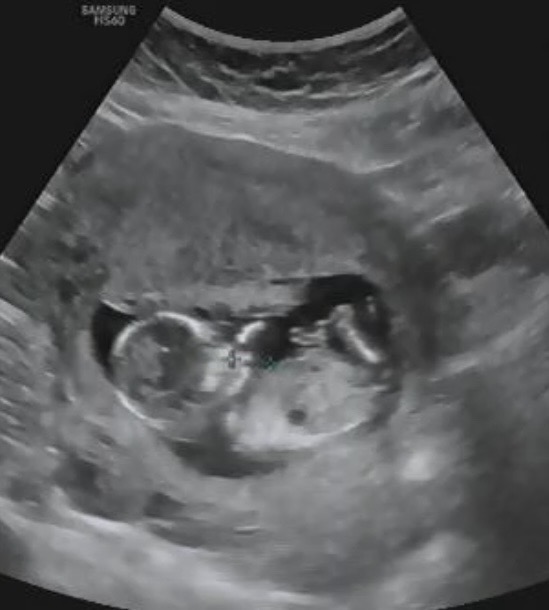

12주인데 성별각도 아시는분? 각도가 남아인가요?여아인가요?

뭔가 각도가 잘 안보이는 촘파 사진 같아요